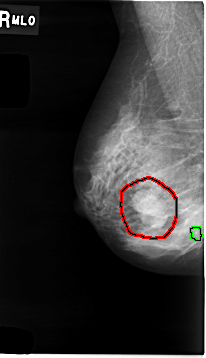

C_0008_1.RIGHT_MLO

RIGHT_MLO LINES 4648 PIXELS_PER_LINE 2672 BITS_PER_PIXEL 12 RESOLUTION 50 OVERLAY

FILE: C_0008_1.RIGHT_MLO.OVERLAY

TOTAL_ABNORMALITIES 2

ABNORMALITY 1

LESION_TYPE MASS SHAPE LOBULATED MARGINS MICROLOBULATED

ASSESSMENT 4

SUBTLETY 5

PATHOLOGY MALIGNANT

ABNORMALITY 2

LESION_TYPE CALCIFICATION TYPE PUNCTATE DISTRIBUTION CLUSTERED

PATHOLOGY BENIGN